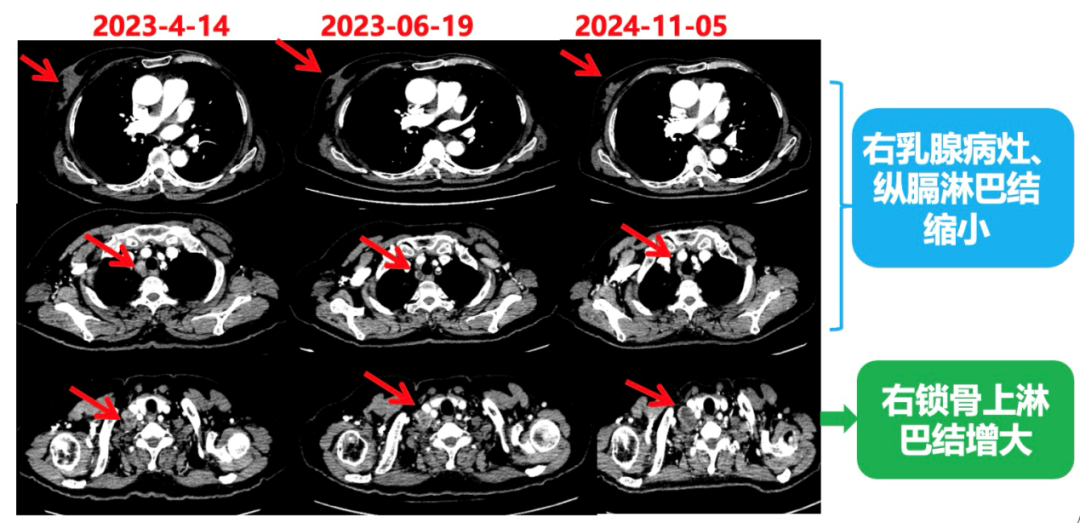

2023.6.26复查PET-CT

1.右乳外上象限乳腺癌病灶(22*16mm),对比2023-04-14 CT(26*24mm)较前缩小,FDG代谢活跃。右侧腋窝小淋巴结(5mm),较前稍缩小,代谢不活跃。右侧锁骨上区、上纵隔淋巴结转移瘤(24*18mm),现大小同前相仿,代谢活跃(SUV:6.7)。

2.现胃贲门部术后改变,术区未见明显异常活性灶。

3.左乳、左侧胶窝术后改变,未见明显异常活性灶。双肺小结节。考虑炎性结节可能,建议复查;双肺门及纵隔另反应性淋巴结。

患者已接受胃癌根治术,术后通过PET-CT对病灶情况进行了评估。目前患者采用哌柏西利联合氟维司群方案治疗,乳腺病灶已明显缩小,但锁骨上淋巴结、纵隔及肺门淋巴结未见缩小。为进一步为患者制定更精准的治疗方案,龚畅教授与曾银朵教授组织了第二次多学科联合会诊。

2024-11-5复查CT:右乳外上象限占位(11mm×9mm),较前明显缩小;上纵隔及右肺门多发淋巴结转移缩小;右锁骨上区淋巴结较前增大。余部位未见肿瘤转移及复发征象。

影像科:CT显示右侧锁骨上区病灶增大主要表现为液化坏死改变,考虑为治疗后改变而非肿瘤进展所致。